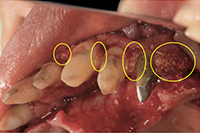

-

治療前の状態です。

歯ぐきが退縮し(歯ぐきが下がり)、歯の根が露出しています。 -